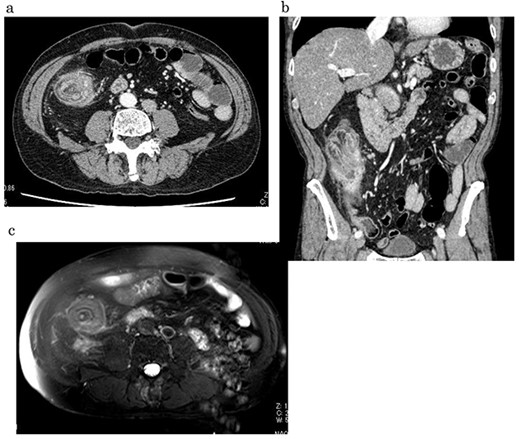

A 59-year-old man was followed up for a year by a dermatologist for psoriasis vulgaris. During this time, he suffered repeated occurrences of cecal diverticulitis diagnosed by contrast-enhanced computed tomography (CT) and was referred to our department for detailed examination and treatment. On examination, he had symptoms associated with subileus such as abdominal distension and pain. Colonoscopy showed a mass with circumferential stenosis in the ascending colon. The surface of the mass showed vascular congestion without malignant findings (Fig. 1a,b). An endoscope could not pass through the stenosis, and enema colonography showed complete stenosis (Fig. 2). Contrast-enhanced CT/magnetic resonance imaging (MRI) revealed a thick wall from the ileocecal region to the ascending colon, which was accompanied by a ring-shaped, layered appearance of mucosal and muscular layers (Fig. 3a–c).

Contrast-enhanced CT/MRI showed increased wall thickness from the ileocecal region to the ascending colon (a, b), which was accompanied by a ring-shaped and layered appearance of the mucosal and muscular layers (c).